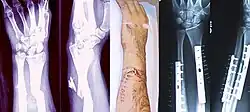

Radiography to identify possible fractures after a knee injury

A bone fracture may be diagnosed based on the history given and the physical examination performed. Radiographic imaging is often performed to confirm the diagnosis. Under certain circumstances, radiographic examination of the nearby joints is indicated to exclude dislocations and fracture-dislocations. In situations where projectional radiography alone is insufficient, Computed Tomography (CT) or Magnetic Resonance Imaging (MRI) may be indicated.